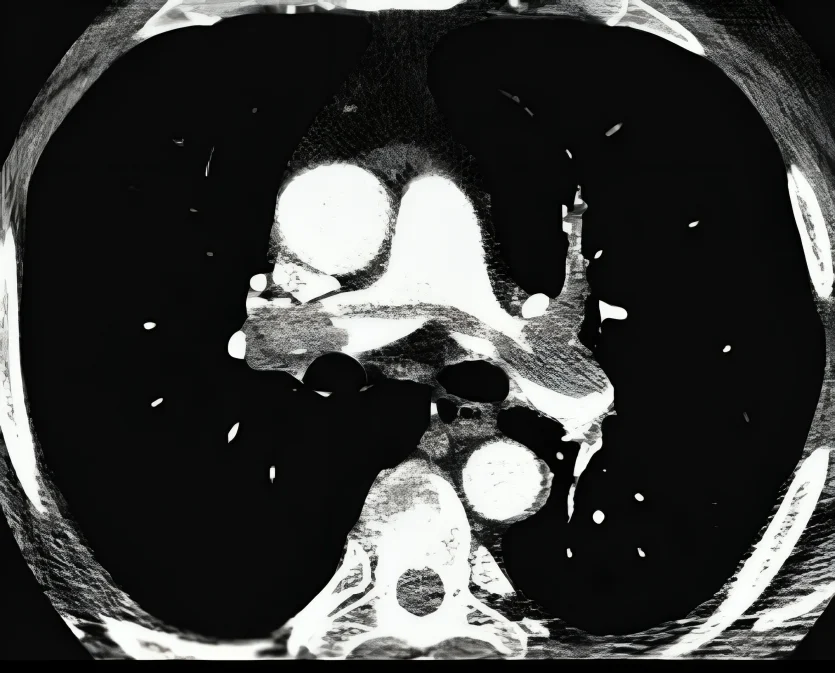

The AHA and ACC have overhauled how we classify acute pulmonary embolism, moving away from the old massive/submassive/low-risk labels and into a far more clinically useful A–E model. It’s the first time the guideline framework actually mirrors what we see at the bedside in managing PE patients.

What I appreciate most is the focus on physiology. RV strain, biomarkers, and respiratory compromise now carry real weight in determining risk stratification. The addition of the respiratory modifier is especially important, anyone who manages PE knows that hypoxia often tells the story before physiologic hypotension does.

The new categories also give us a clear home for the patients who aren’t in shock yet but are headed there, which has always been a gray zone. This alone will improve communication across PERT teams and help with faster, more consistent decision making.